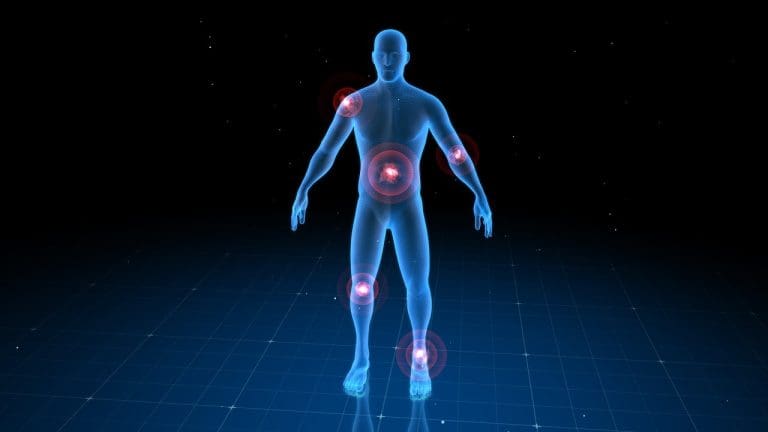

Common Flare Up Symptoms Across Autoimmune Conditions

Knowing the symptoms of autoimmune flare-ups is key to managing them well. Diseases like rheumatoid arthritis, lupus, and multiple sclerosis can cause many symptoms. While each disease is different, there are some symptoms that many people share.

Joint Pain and Inflammation

Joint pain and inflammation are common in many autoimmune diseases, like rheumatoid arthritis. The immune system attacking the joints causes pain, swelling, and stiffness. This can make it hard to move and affect your life a lot.

- Pain and stiffness in the hands, feet, and other joints

- Swelling and redness around the affected joints

- Reduced range of motion and flexibility

Understanding flare-ups in autoimmune diseases needs a deep look at each condition’s symptoms. These diseases can hit different parts of the body, causing many kinds of flare-ups.